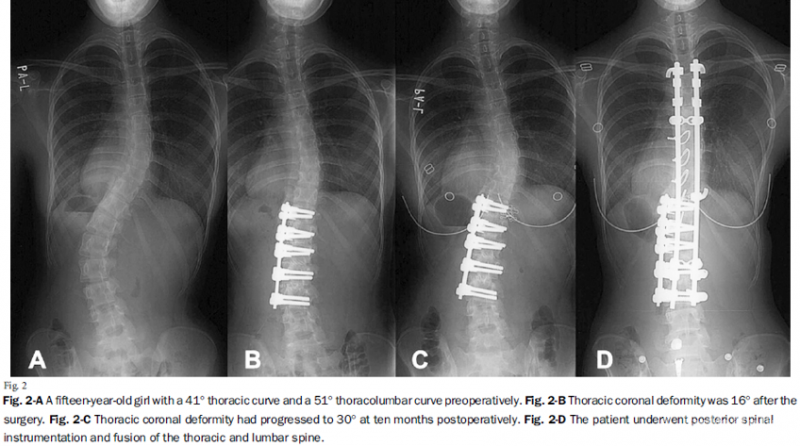

4.在胸腰段/腰段选择性融合矫正后,胸段弯曲并非都能获得良好的代偿矫正。对于胸段弯曲>40°,且胸腰段/腰段弯曲与胸段弯曲之比<1.25的患者,应行后路手术融合双弯,以避免单纯前路矫形术后胸弯失代偿。

图8.胸弯>40°、胸腰段弯曲与胸段弯曲之比=1.24(<1.25)术后胸弯失代偿